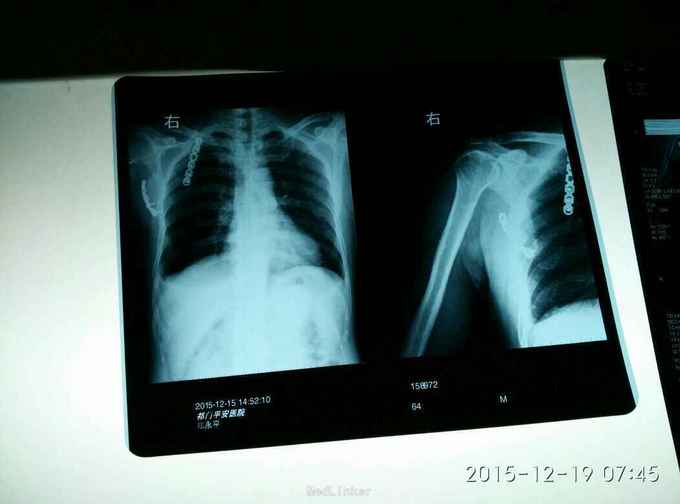

右肩峰及肩胛骨骨折

骨折 肩峰骨折 肩胛骨骨折

外伤致右胸疼痛及右肩疼痛,活动受限1天入院。去年右肩胛骨骨折在外院行切开复位内固定术。

胸廓挤压试验阳性,右肩峰压痛阳性,右肩主动活动受限,外展约30度。x片及CT示右肩峰骨折及肩胛骨骨折,右第6.7.8.9肋骨骨折。

右肩峰骨折,右肩胛骨骨折,右第6.7.8.9肋骨骨折